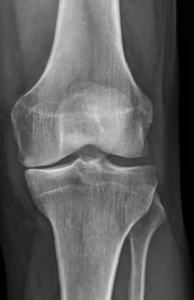

Le diagnostic repose sur un faisceau d’arguments cliniques (interrogatoire, examen physique) et sur l’imagerie (pincement de l’articulation, présence d’ostéophytes ou « becs » osseux). Lorsque ces signes sont présents, il n’est pas nécessaire d’effectuer d’autres examens à visée diagnostique que la radiographie standard.

Lorsque l’usure du genou atteint 2 ou 3 compartiments (gonarthrose tricompartimentale) (Fig.7)